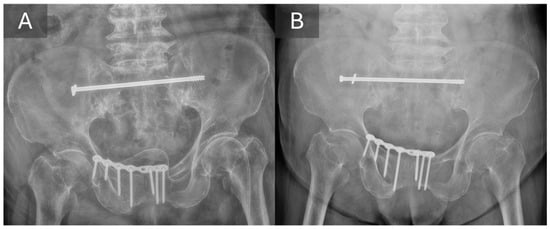

3.3. Radiographic Outcomes